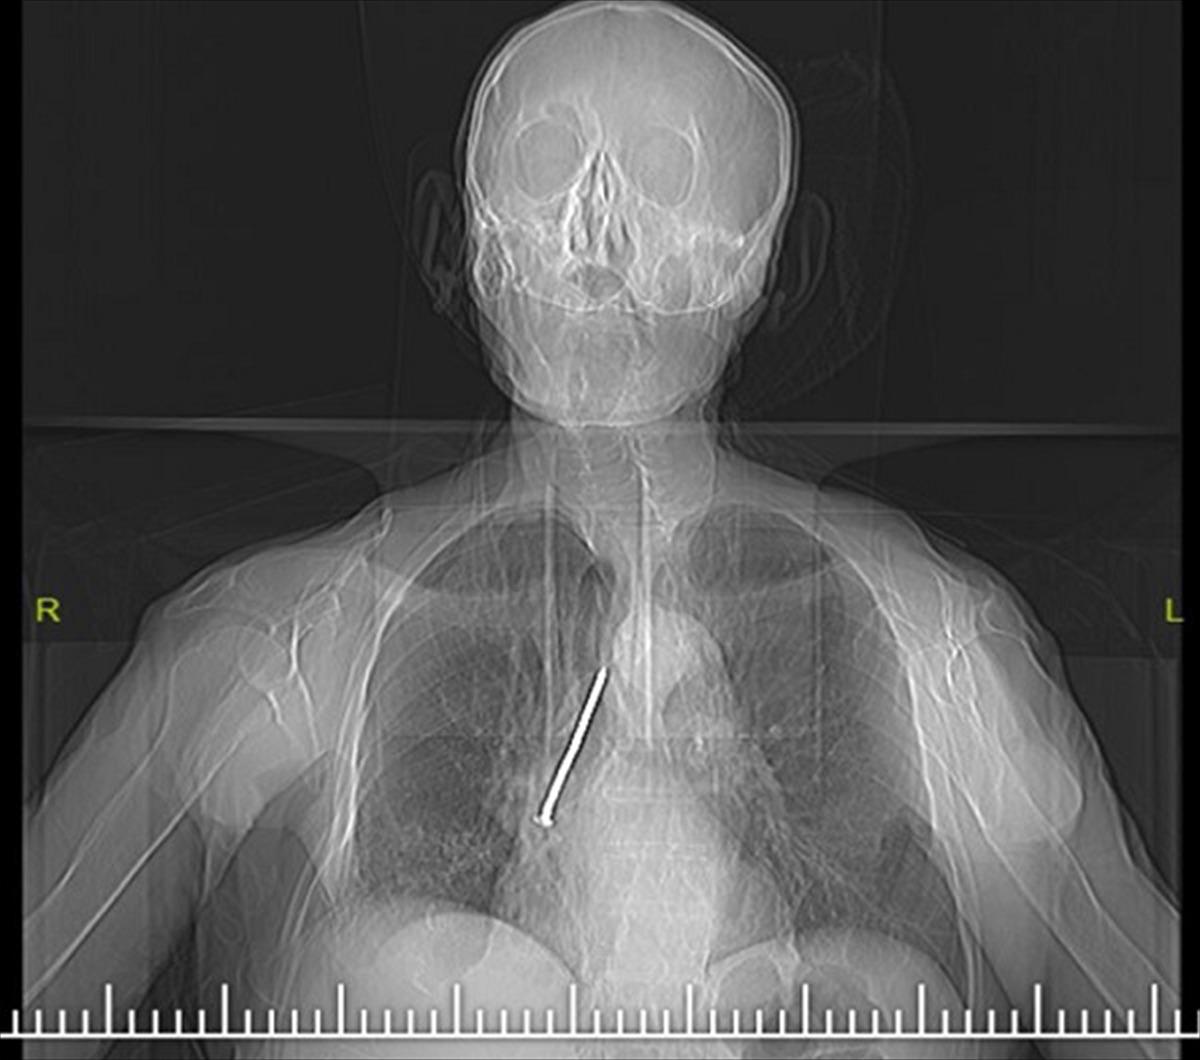

Elazığ'da öksürük ve nefes darlığı şikayetiyle hastaneye başvuran Keko Ateş'in (91) nefes borusunda 10 santimlik çivi tespit edildi. Ateş'in, 24 yıl önce Larenks kanseri ameliyatı sırasında nefes borusunda açılan açıklığı temizlemek için kullandığı çivinin soluk borusuna kaçtığı belirlendi.

Keko Ateş, öksürük ve nefes darlığı şikayetiyle Fethi Sekin Şehir Hastanesi'ne başvurdu. Yapılan tetkik ve muayenelerden sonra Ateş'in nefes borusunda çivi olduğu tespit edildi. Hastanın hayatını tehlikeye atan bu durumun giderilmesi için Ateş, Göğüs Cerrahi Uzmanı Dr. Öğr. Üyesi Murat Kılıç tarafından operasyona alındı. Soluk borusun içerisinde ve sağ akciğer içerisine doğru kaçmış olan 10 santim uzunluğundaki çivi, 'Rijit Bronskoskopi' işlemiyle çıkarıldı.

Dr. Öğr. Üyesi Murat Kılıç, Larenks kanseri olan Ateş'in, 24 yıl önce Total Larenjektomi ameliyatı sırasında boynundan nefes borusuna açılan açıklığı temizlemek için kullandığı çivinin soluk borusuna kaçtığını anlattı. Dr. Öğr. Üyesi Kılıç, "Bu nedenle gelişen öksürük ve nefes darlığı şikayeti ile önce başka bir sağlık merkezine başvuran, ardından Fethi Sekin Şehir Hastanemiz Göğüs Cerrahisi Kliniği'ne yönlendirilen hastaya çektiğimiz tomografide soluk borusu içerisinde ve sağ akciğer içerisine doğru kaçmış olan bir çivi olduğunu tespit ettik. Bunun üzerine hastamızı acil olarak ameliyata aldık. Uyguladığımız Rijit Bronskoskopi işlemi ile nefes borusundaki 10 santimlik çiviyi başarılı bir şekilde çıkardık. Hastamızı ameliyat sonrası bir süre serviste takip ettikten sonra gün içerisinde şifa ile taburcu ettik" dedi.